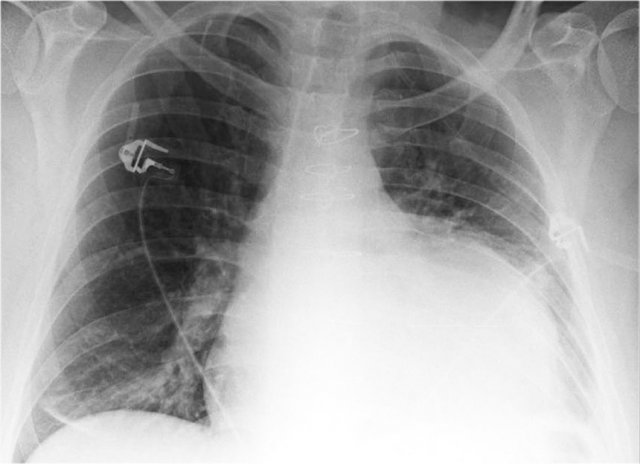

Cardiac Pacemakers

There are various types of cardiac pacing devices, each with specific lead configurations.

In this example:

• Right atrial lead

• Right ventricular lead

• Left ventricular lead via the coronary sinus (used in cardiac resynchronization therapy)

Indication for cardiac resynchronization therapy:

• Patients with ventricular dyssynchrony benefit from biventricular pacing, which improves ventricular coordination and enhances cardiac output.

More on cardiac pacemakers...